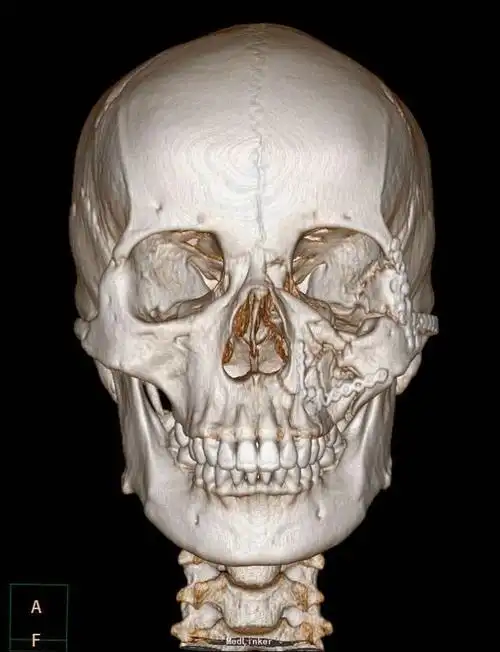

【病例讨论】上颌骨骨折何以引起张口受限 [病例帖]

【急诊】颧骨骨折,上颌骨骨折ct表现

上颌骨骨折

上颌骨骨折 [病例帖]

左颧骨复合体,上颌窦前壁骨折一例

正颌手术# le fort ii型骨折:又称上颌骨.